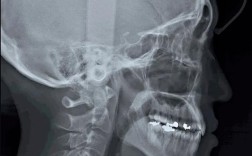

头颅侧位片是正畸诊断中至关重要的影像学检查,它提供了骨骼结构、牙齿位置、面部软组织轮廓以及气道等多维度的信息,是制定正畸治疗计划的基础,拍摄时精确的定位是获得可靠诊断信息的关键,以下是拍摄头颅侧位片的详细步骤和要点:📍一、目的与重要性骨...